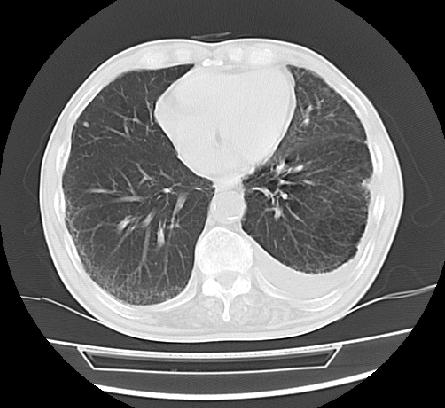

以下是引用ct诊断高手在2009-5-29 13:50:00的发言:[br]考虑左侧中央型肺癌,阻塞性肺炎伴肺不张。纵隔淋巴结转移。慢支 肺间质纤维化肺气肿。左侧胸腔积液。左侧肋骨转移?

以下是引用hhcckk在2009-5-29 14:58:00的发言:[br]左上周围型肺癌,左肺门、纵隔淋巴结转移,左侧胸腔积液,左侧肋骨转移[br]